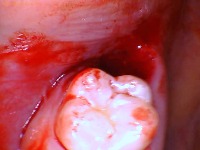

This picture is of two extracted wisdom teeth:

These are two intraoral photos of what both of the extraction sockets that the two teeth came from: